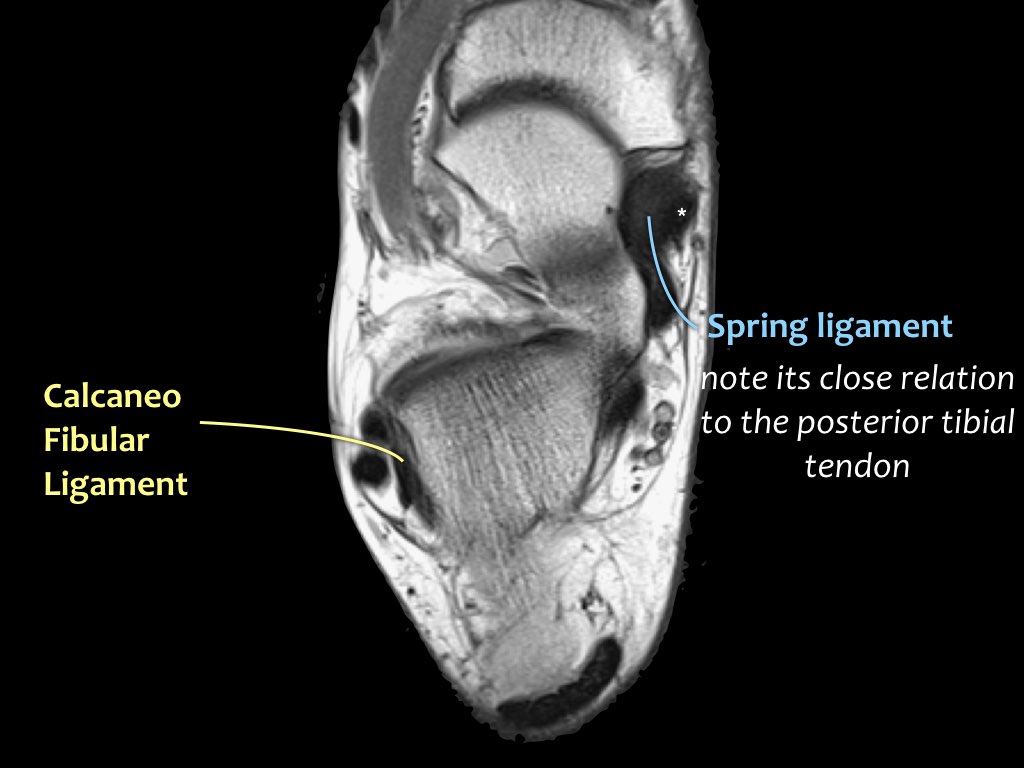

Khi gân chày sau bị tổn thương, cần kiểm tra kỹ dây chằng lò xo (spring ligament), vì cả hai cùng nhau duy trì vòm bàn chân ở phía trong.

Trong biến dạng bàn chân bẹt, cả gân và dây chằng lò xo đều có thể bị tổn thương.

Các hình ảnh cho thấy bệnh lý gân chày sau (PTT), đồng thời có tổn thương dây chằng lò xo kèm theo.